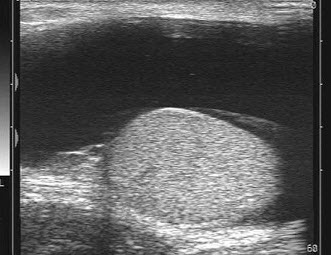

56、单项选择题

某男,因左阴囊疼痛不适数日,B超检查声像图如下,根据彩色声像图及血流特征,最可能的诊断为()

A.睾丸肿瘤

B.睾丸结核

C.睾丸炎

D.睾丸扭转

E.附睾炎